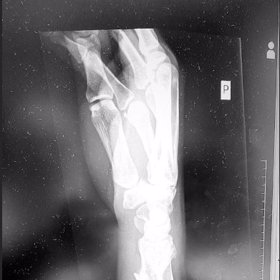

„Není to nic moc období. Ale nerozcházím se, to ne. Jen spolu nejsme moc často, má hokej, já práci, já v Brně, on v Popradě, do toho ta ruka, sama na narozeniny, tak na mě padl splín. Mám zlomené zápěstí, narovnávali mi kosti, byla to šílená bolest,“ řekla eXtra.cz na vysvětlenou brněnská influencerka.

„Pozitivní je, že ruka se zahojí. Zaplaťpánbůh, že to není nic horšího. Jela jsem poslední kopeček na snowboardu, s kamarádem jsme dělali blbosti a pak jsem bohužel špatně spadla. Kromě snowboardu nesportuju, tím pádem teď pro mě skončil veškerý sport. Takové zvedání skleniček s něčím dobrým je dostatečný sport. Na biceps ideální,“ dodala už s náznakem lepší nálady.